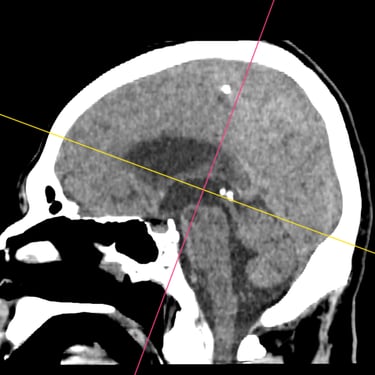

Hidrocefalia – Colocación de derivación ventriculoperitoneal (DVP).

La hidrocefalia es una condición neurológica causada por la acumulación anormal de líquido cefalorraquídeo dentro de los ventrículos cerebrales, lo que genera aumento de la presión intracraneal y deterioro neurológico progresivo. La colocación de una derivación ventrículoperitoneal (DVP) es el tratamiento quirúrgico más utilizado para controlar esta patología. Este sistema permite drenar el exceso de líquido desde el cerebro hacia la cavidad abdominal, donde se reabsorbe de manera segura. La intervención oportuna alivia los síntomas, previene daño cerebral y mejora la calidad de vida del paciente.